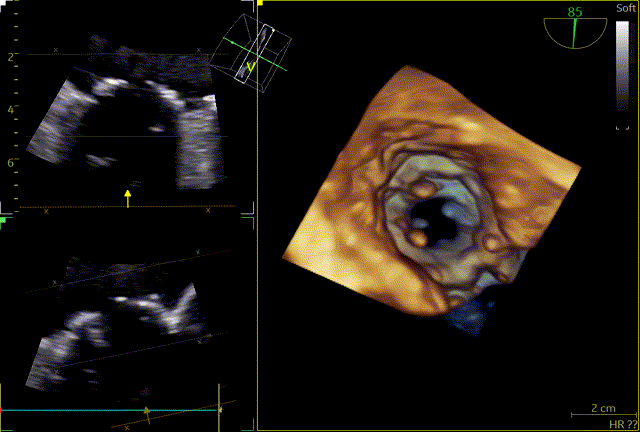

术后即时食道超声示:二尖瓣未见瓣周漏,生物瓣功能良好,三尖瓣未见明显返流。

术后床旁超声描述:MVR+TVP术后,双房增大。二尖瓣位为人工生物瓣回声,瓣环位置固定,瓣叶活动良好,未见赘生物回声。PHT法测二尖瓣人工生物瓣口面积:3.8cm²,三尖瓣见成形环强回声,CDFI:未见异常。